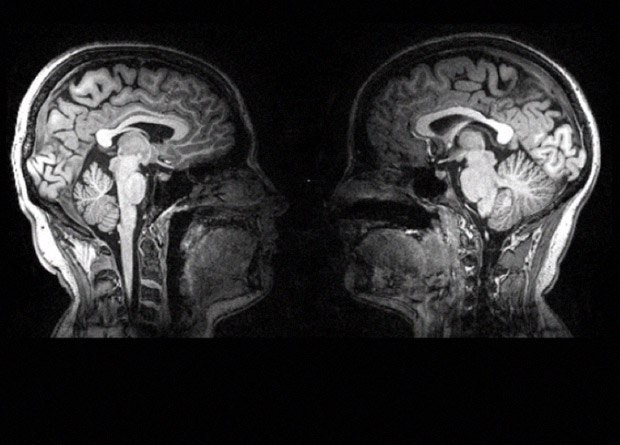

Функциональная МРТ может рассказать о работе мозга очень много, но у этого метода есть свои ограничения. Например, сканер очень громоздкий и очень шумный, а визуализировать можно активность только одного мозга за раз: изучать активность мозга при общении людей с помощью него, поэтому, затруднительно. А вот финским ученым это удалось: они поставили в МРТ двойную катушку, благодаря чему им удалось засунуть в аппарат сразу двоих участников и изучить активность их мозга одновременно. Лежать им, правда, пришлось в обнимку